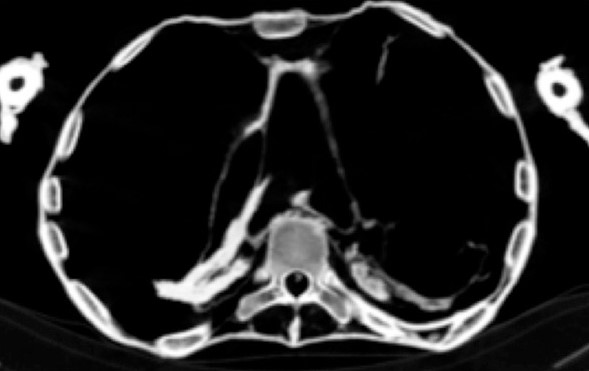

CT扫描的结果表明,“尖叫的妇女的木乃伊”是一名在其第六个十年中死亡的妇女。与Pentawere不同,女人的身体受到了良好的木乃伊治疗。因此,很明显,她的死亡情况是不同的。哈瓦斯说,CT检查结果表明木乃伊患有严重的动脉粥样硬化,从而影响了人体的许多动脉。

他解释说,动脉粥样硬化是一种退行性疾病,会逐渐影响动脉壁,导致腔变窄和血管阻塞。CT扫描显示她患有左右冠状动脉,颈部动脉,腹主动脉和动脉以及下肢动脉的动脉粥样硬化。心脏疾病,尤其是冠状动脉疾病,是现代成年人猝死的主要原因。